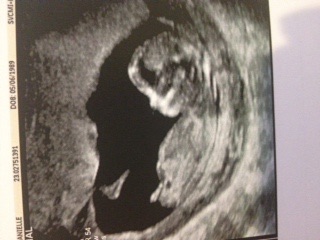

guessing girl

Leaning girl GL!

Girl

I think girl too, congrats!

Girl x Sent from my iPhone using Tapatalk

Pink